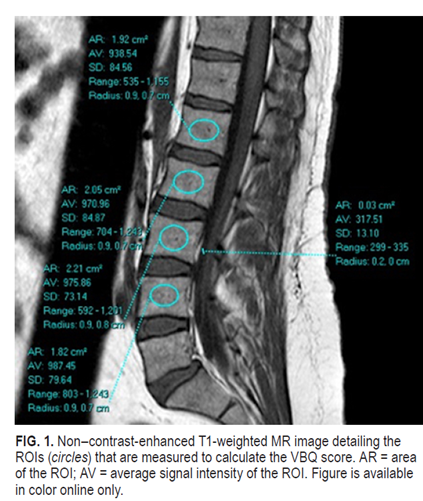

Great work in

@TheJNS#spine by@HopkinsNsgy's@DanielSciubba with rising star medical student & friend,@AKarimAhmed4! An MRI-based tool for bone quality assessment to predict compression fractures in#spineonc!@NSTumorSection@NeuroOnc@youngneuros#neuroonc#neurosurgeryhttps://twitter.com/TheJNS/status/1213430037883629568 …